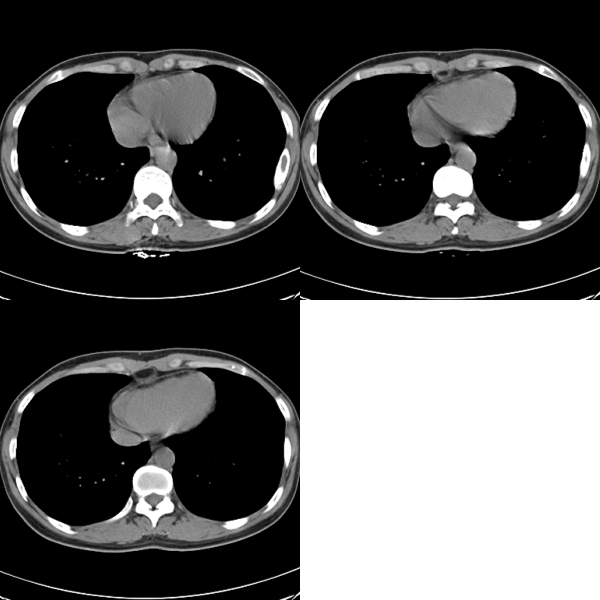

标题: CT19623:F40y,肋骨改变。

40岁女性,双侧胸部疼痛,以左侧为明显1+年。余无明显异常。

左侧肋骨单发膨胀性病变,皮质连续,病史较长,首先考虑良性病变:骨纤可能性大。